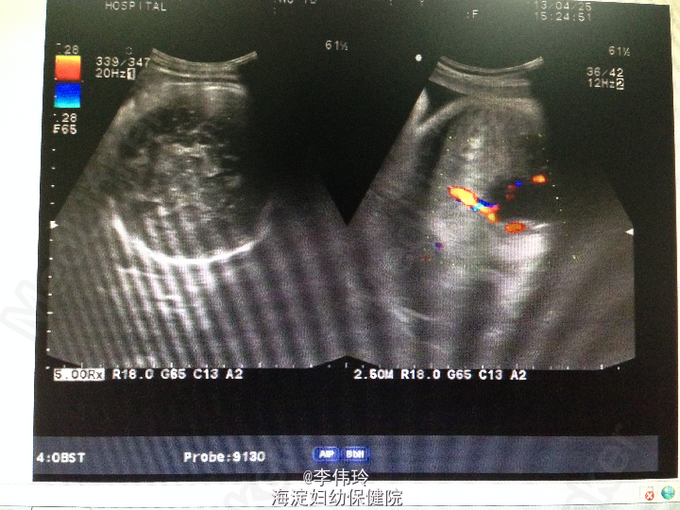

患者因停经29+5周,不规则下腹胀痛3天 收入本院。2013年剖宫产1次。

查体:生命体征平稳,心肺未见明显异常。双下肢无水肿。专科情况:宫高27cm,腹围70cm,胎心音154次/分,扪级无宫缩。 辅助检查:B超:活单胎,头位,相当孕29周(BPD7.2cm,FL5.7cm),羊水量未见异常(最深6.8cm)。胎盘成熟度0+度,胎盘下缘距离宫颈内口约4cm,未除外植入膀胱。余检查未见异常。

诊断:凶险性边缘性前置胎盘伴植入 治疗:继续吸氧,口服地屈孕酮等待产治疗。现患者一般情况可,予出院。